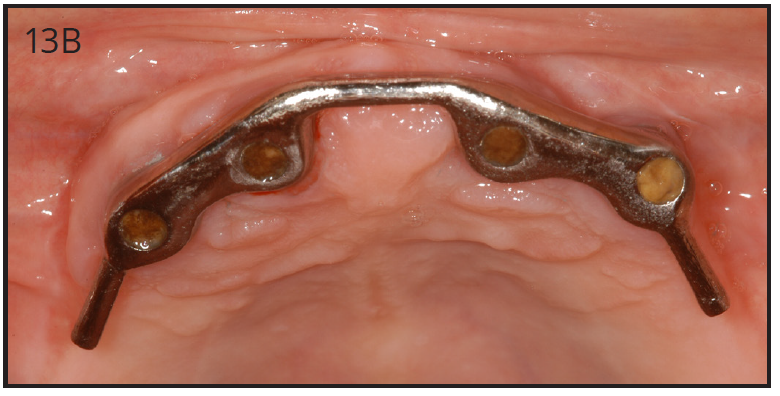

As stated earlier, dentures replace only about 10% of chewing function. This causes digestive problems, due to an inability to chew food properly, also leading to malnutrition, due to an increase in consumption of softer, more processed foods. This inability to chew also results in atrophy of the alveolar arches due to lack of adequate pressure on the bone. When the denture is pressing on the mental foramen, then patients will experience pain and numbness of the lower lip. A good solution for these denture wearers is to place 2 to 4 implants in the mandible to stabilize the denture. The denture is then attached to the implants via snap-on attachments or a bar. (Figures 13A-C) According to the 2002 McGill Consensus Statement on Overdentures, mandibular two-implant overdentures are superior to conventional dentures in all clinical trials, even up to nine years in function.32

Figure 13B – Maxillary bar that attaches the overdenture

Figure 13B